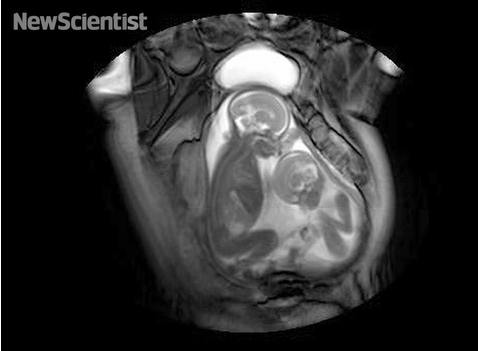

Снимка со магнетна резонанца на близнаци во стомакот на мајката.

- Видео: Неродени близнаци снимени со магнетна резонанца, восхитувачки јасна слика